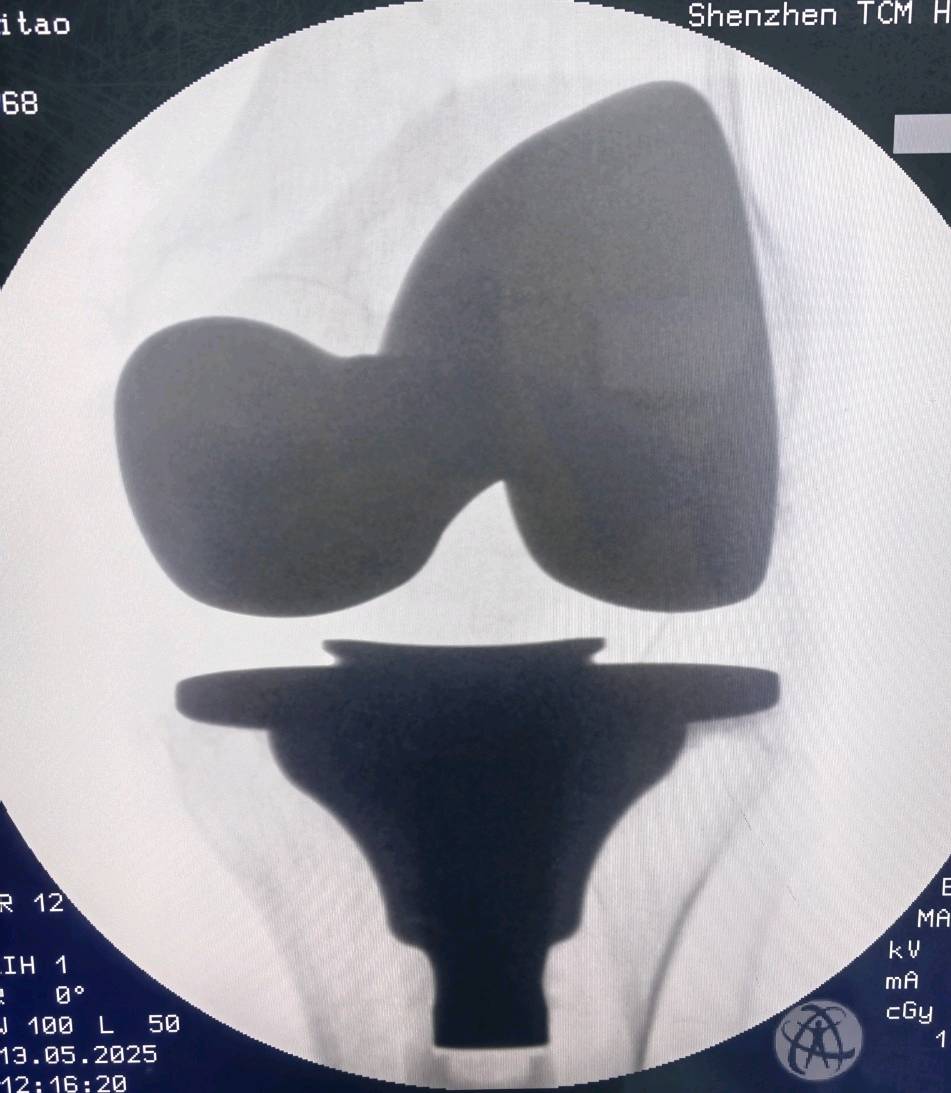

2. 对“换膝盖”的想象过于可怕: 部分老人以为手术是把整个膝盖骨都挖掉,换成一个金属疙瘩,想象起来非常恐怖。实际上,手术是精确地置换关节的磨损表面。